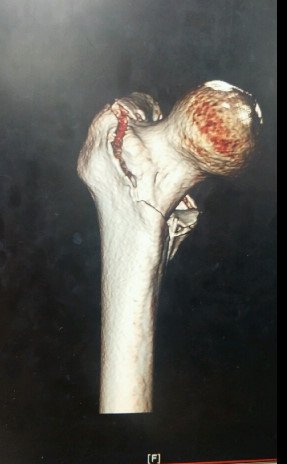

저는 실려가서 허벅지 뼈가 부러지는 대퇴골 골절상을 비롯해 가슴 팔 다리 부분이

찢어지는 상해를 입었습니다. 다시 큰 대학병원으로 옮겨서 대퇴골 골절 수술을 했습니다.

철심 길게 하나 양쪽으로 2개 핀1개꽂고 대수술을 했습니다. 수술걸린시간은 5시간정도고요

않았는데.. 그리고 얼마나 심각하게 넘어져서 다쳤으면 젊은 사람들이 거의 부러지지않는

허벅지 뼈가 부러져서 의사들이 다 놀랬을정도인데.......

여기에 오른발 짚는 순간 떨어져서 오른쪽 허벅지가 아주 작살이 났습니다.